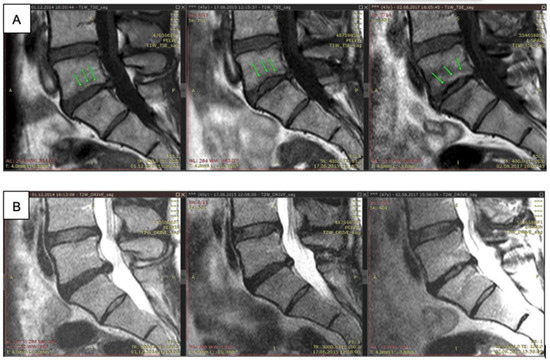

4.2. LRD after Surgical Interventions on the Spine as a Means of Preventing the Development of Recurrent Disc Herniation, Instability of the Affected Segment and Further Development of the DDD

- Baskov, A.V.; Drakin, I.A.; Dreval, O.N.; Baskov, V.A.; Shekhter, A.B.; Sobol, E.N.; Drakin, A.I. Nonablative laser irradiation of the intervertebral discs as a method of reduction of recurrent disc herniations. Pac. Med. J. 2015, 4, 29–31. [Google Scholar]

- Borshchenko, I.; Sobol, E.; Shekhter, A.; Baskov, A.; Grin, A.; Borshchenko, M. Biological non-ablative repair of lumbar discs by transforaminal intradiscal laser irradiation: MRI quantitative analysis of the effects—Preliminary report. Lasers Med. Sci. 2020, 11. [Google Scholar] [CrossRef]